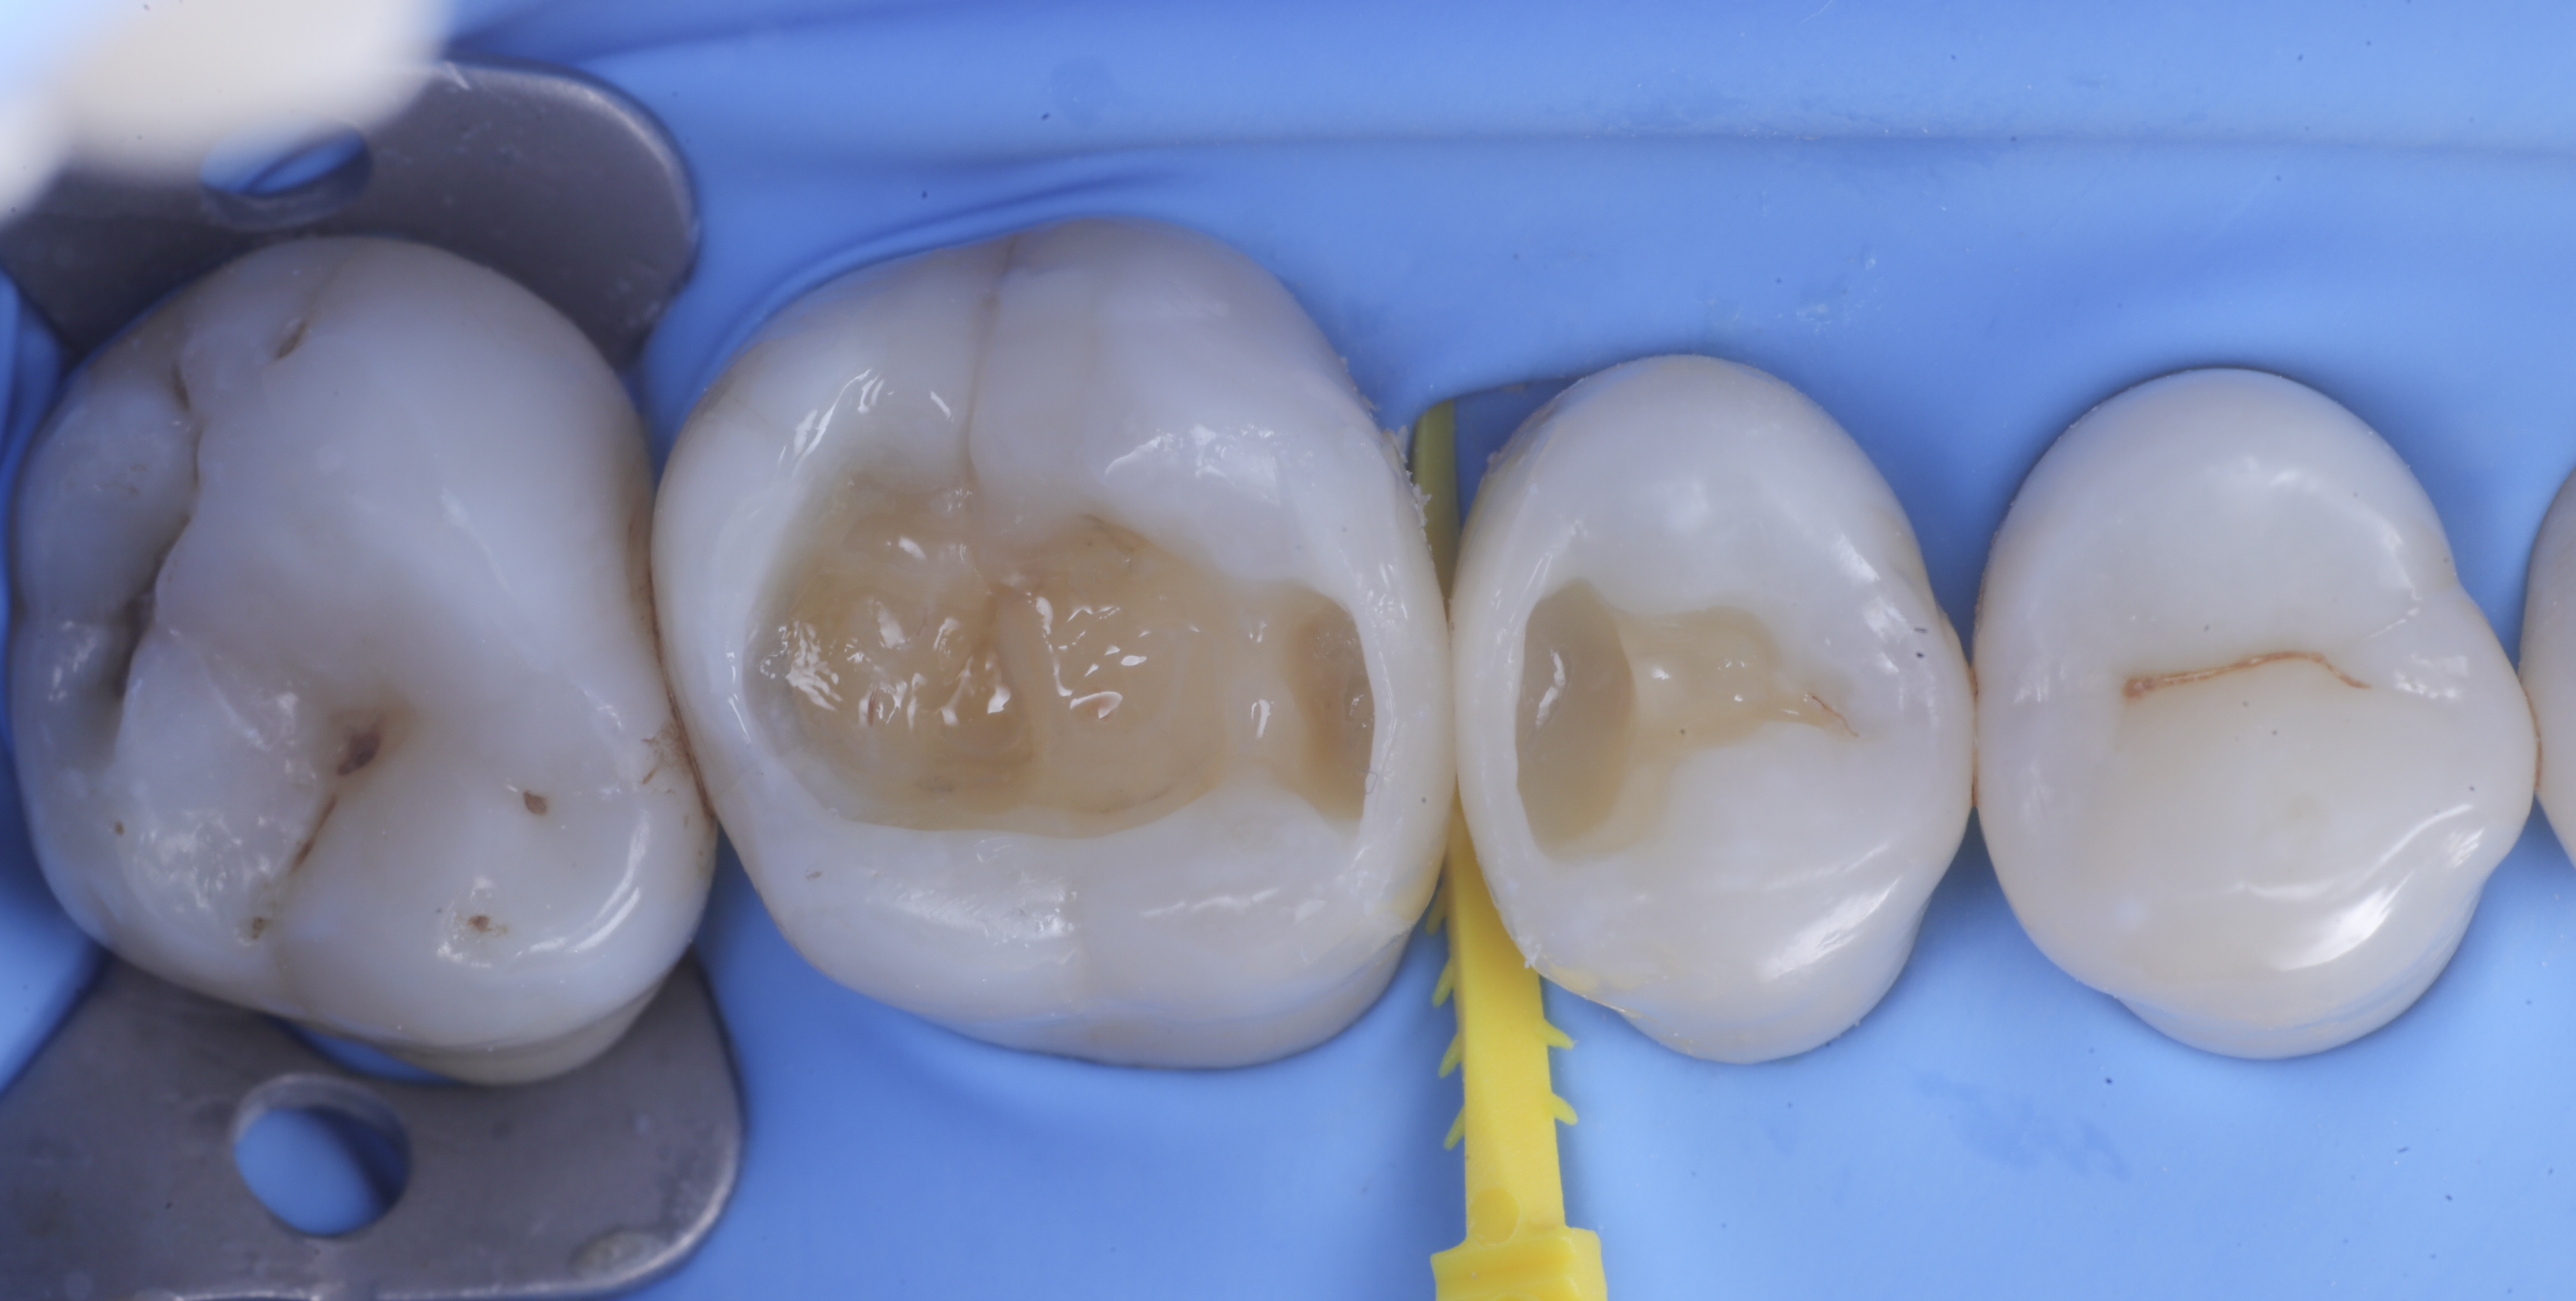

foto 1 Fotografia iniziale

foto 2 Isolamento e aspetto delle cavità ultimate